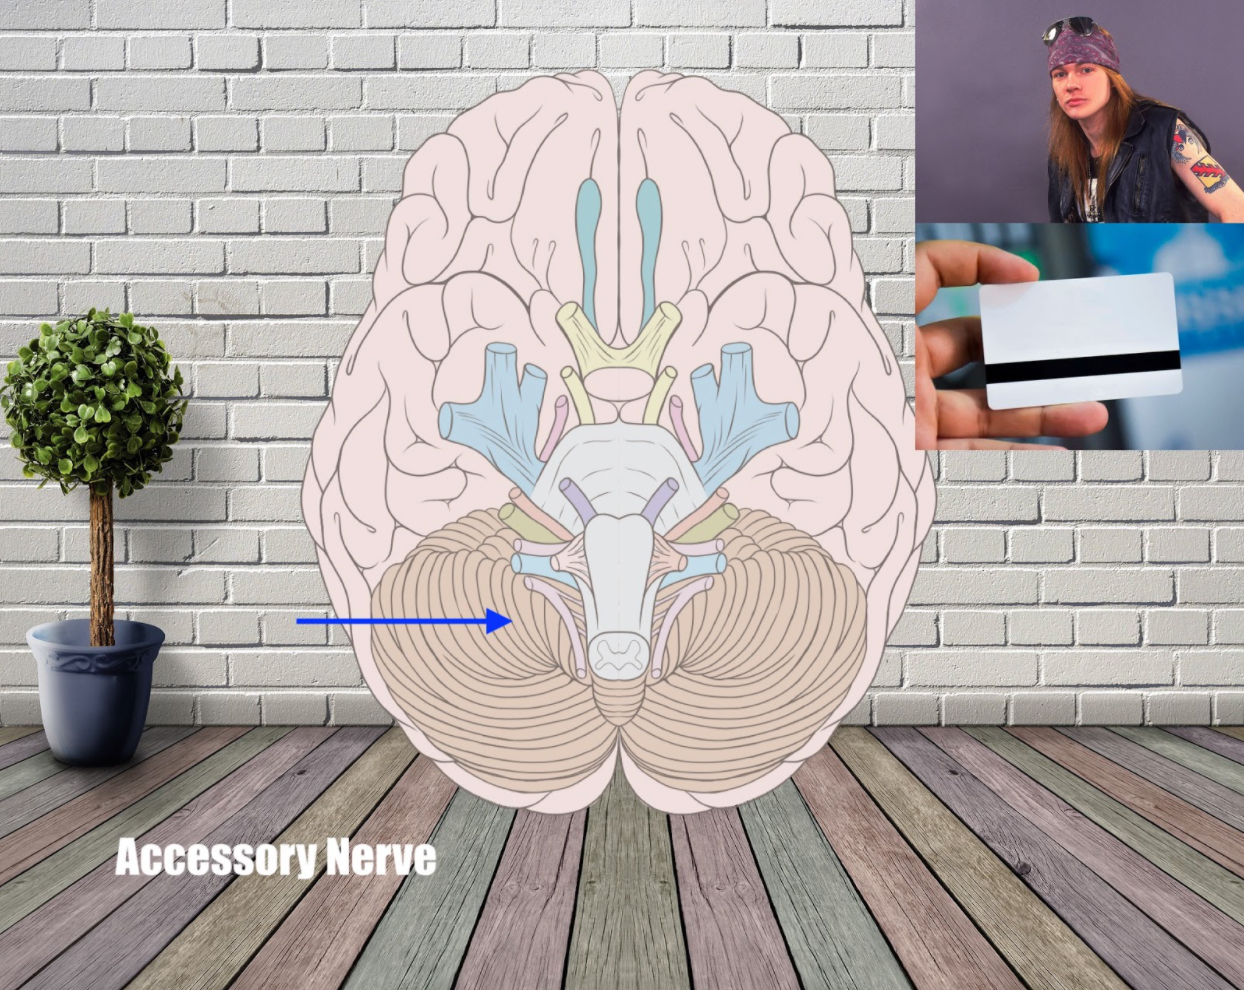

Accessory nerve (Motor) – ‘Axel Rose, All-Access Pass’

This nerve controls the sternocleidomastoid and trapezius muscles.

Taking a name that sounds like “access” and giving that person an all-access pass will help you remember it. How about Axel Rose, who is associated with backstage passes?

To add facts about the sternocleidomastoid, you can add associations like Howard Stern. By now you should be starting to get the idea. The alphabet is a tremendous helper when you want to find associations.